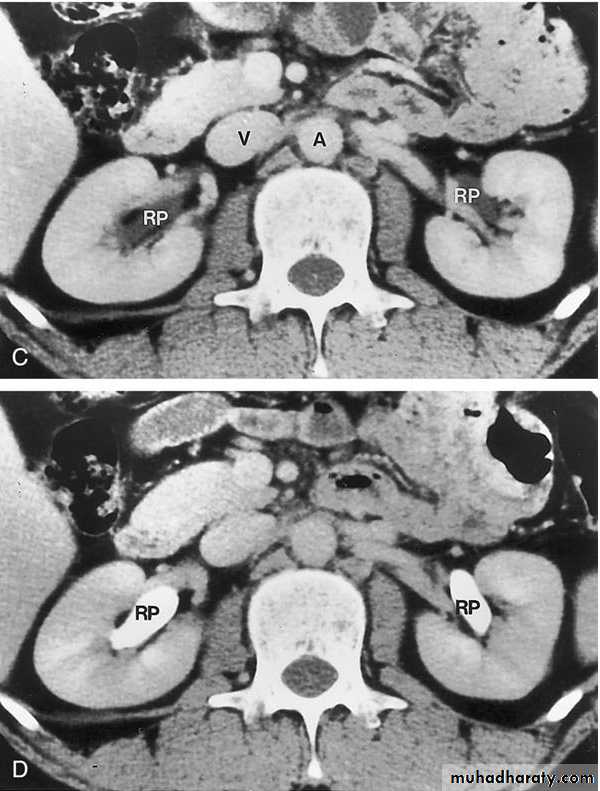

COMPUTED TOMOGRAPHY ( CT scan)

Non Contrasted (Native, non enhanced)Contrasted: Oral Contrast Agents

Intravenous Contrast Agents

CT scan accurately characterize the nature of tissue in the lesion.

CT is useful in the preoperative evaluation and staging of tumors.CT has replaced IV urography as the primary modality for the assessment of suspected renal injuries and their complications

For the evaluation of patients with acute flank pain, unenhanced spiral CT is more sensitive in detecting calculi than EXU. (except indinaver no radiolucent stones).

Drawbacks: Expensive, more radiation, not always available, need experience, contrast contraindications, pregnancy